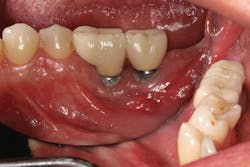

Implant manufacturing involves a high degree of precision. Implant fixture dimension, bone drill protocols, taps, and insertion devices should intimately correspond. Prosthetic components, abutment connections, and screws are also closely mated in design and production, so there is minimal tolerance between machined components. Interestingly, I hear much conversation regarding the poor fit of lower-tiered implant components, which can result in implant failure or screw loosening. Implant systems consist of CAD/CAM parts, with components that are fabricated with a high degree of homogeneity. Vertical and anti-rotational discrepancies exist and vary between companies and the types of connection used,12 but studies indicate that the fit of mismatched components improves with the application of mechanical torque to a clinically acceptable level.13 Clinicians also need to understand that there is more to screw loosening than the system-such as passive fit of the casting, proper torque values and preload,14 adequate interproximal contact, and the most often overlooked and misunderstood aspect of dentistry . . . occlusion (figures 7-9).

Figure 7

Figure 8

Figure 9

Figures 7-9: Implant site No. 19 has been restored for one year without any incident of screw loosening. Bone levels are excellent (figure 7), but a small gap is evident between the abutment and fixture platform upon radiographic evaluation (figure 8), due to the usage of implants from two "compatible" manufacturers. The tissue levels are excellent, despite a "mismatch" in components. Notice the gingival recession and the lack of attached tissue15,16 on distal implant site No. 18 (figure 9). However, with critical examination of implant No. 18, it is possible that the transmucosal element is too long and the overlying gingival tissues too thin, making this particular fixture inappropriate for this site. (Perhaps a bone-level fixture would have been a better choice.)